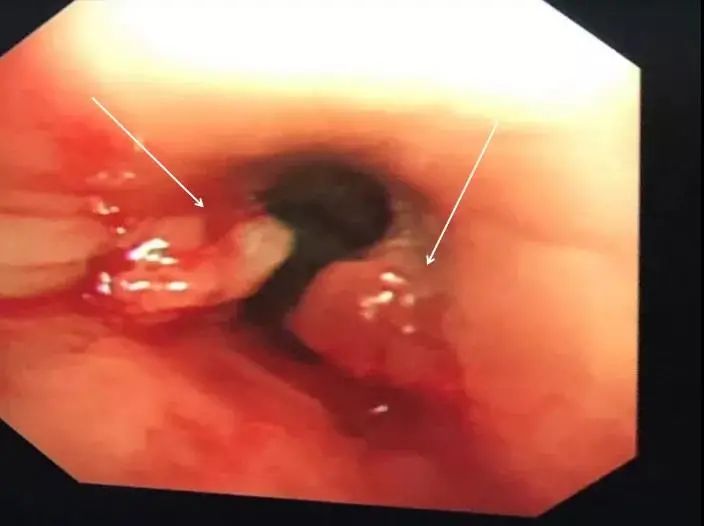

为了明确杨叔肺的情况,也为了打消杨叔的疑问。在充分评估病情后,选择做了纤维支气管镜。气管镜一开始看到左支气管的异物以为是个金属,好像螺丝钉、假牙之类的,旁边因为异物长期刺激还长出了肉芽。

谭锦文主任医师解释,“再晚点肉芽会把左边支气管完全堵塞,导致肺不张,肺通气不足,严重可引起呼吸衰竭、反复感染”。经过谭锦文主任的娴熟操作,异物很快被安全地钳取出来。

-异物取出后看到增生的肉芽肿-